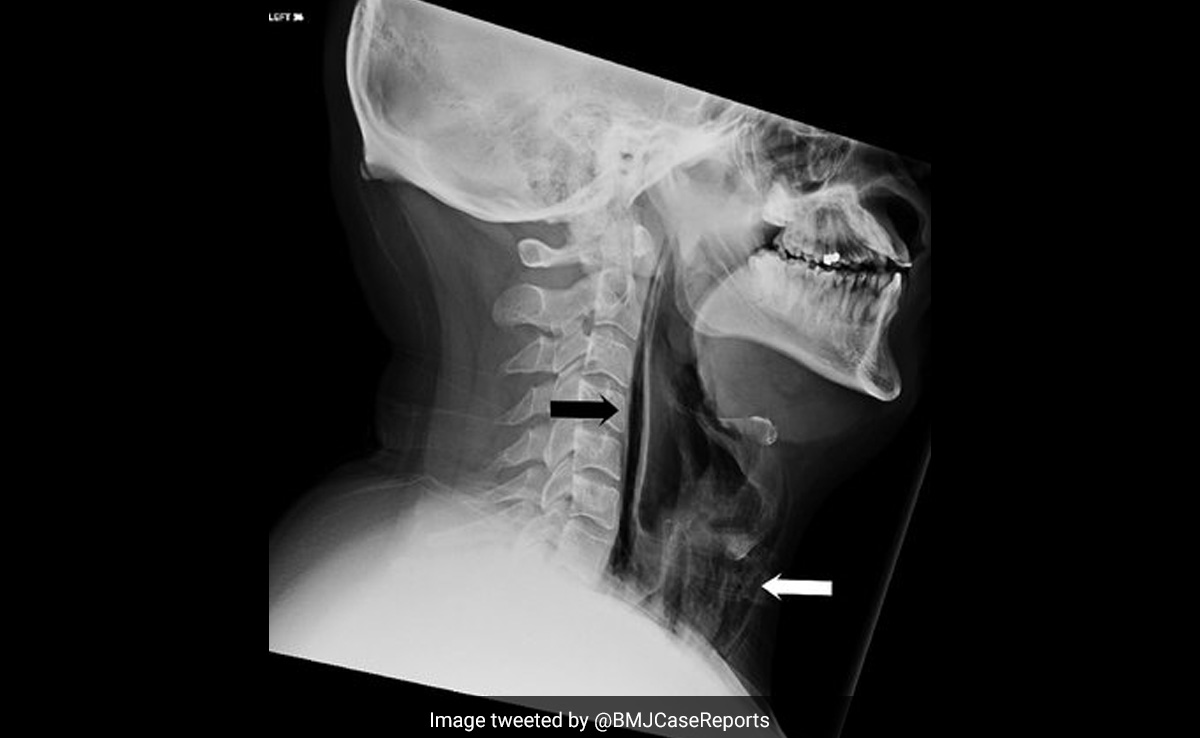

डॉक्टरों ने कहा कि हवा की धारियाँ उसके गले के कुछ ऊतकों में फंस गई थीं और उसका गला फट गया था. ग्रसनी का स्वतःस्फूर्त टूटना बहुत दुर्लभ है, जो आमतौर पर उल्टी, मतली, भारी खांसी या किसी प्रकार के आघात के कारण होता है.

गर्दन के अंदरूनी में किसी भी संक्रमण के जोखिम या प्रगति से बचने के लिए उस शख्स को चिकित्सकीय निगरानी में रखा गया था. मरीज को एक फीडिंग ट्यूब और एंटीबायोटिक्स दी गईं. दो सप्ताह के बाद वह ठीक हो गए और नरम भोजन खाना शुरू कर दिया.